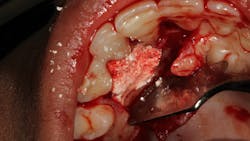

Another scenario that took place in a private practice with actual dollar amounts can be seen in treatment plan C. This patient had already paid for treatment plan B in the $5,000–$7,000 range and subsequently presented to the practice with moderate peri-implantitis. In addition to the money the patient had already invested, she would now be responsible for the financial costs of treatment plan C.

After reviewing the additional costs and lengthy healing time involved with surgery to correct the ailing implant, the overall costs associated with treatment were in the $8,000–$10,000 range, with more than three years of treatment time invested. Of important note is that most insurance companies limit the amount of reimbursement for implant-related services. When dealing with insurance companies, accurate ADA coding and claims submission are critical to facilitate services and expedite reimbursement.